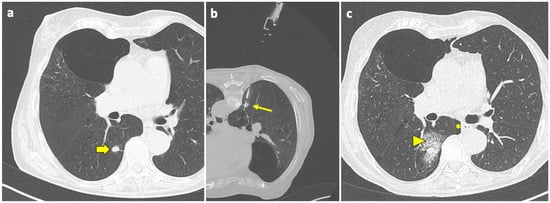

Pulmonary hemorrhage is the second most common complication after PTLB, with a prevalence ranging from 4 to 27% [94]. In the majority of cases, this complication is mild and only detected on the post-biopsy CT scans as ground-glass opacity (GGO) around the lesion or along the needle tract, representing an alveolar hemorrhage in clinically asymptomatic patients, as shown in Figure 3.